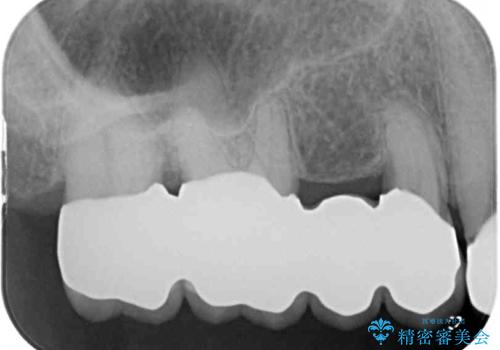

処置後はオールセラミックブリッジにて補綴し、再発防止のために就寝時にナイトガード(マウスピース)を装着していただくこととしました。

歯槽骨の再生には1年ほどの待機期間を要し、その後のポケット除去処置も数か月の待機期間を必要とするため、治療期間は長期に及びました。

治療途中からマウスピースを装着していただくことで、歯槽骨の回復も順調に進みました。

術後に痛みの続く処置を2度も受けていただくこととなりましたが、処置後は出血などの気になる症状がなくなり、患者様には大変満足していただきました。